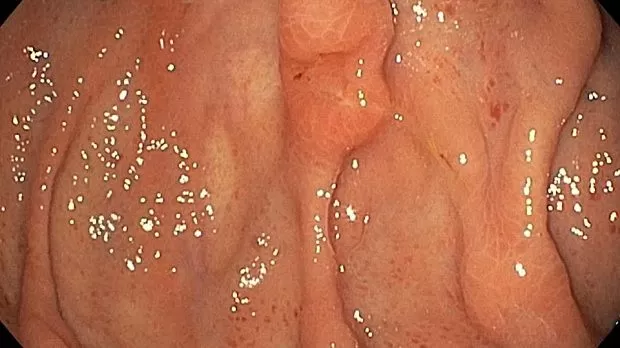

Публикации из социальных сетей: “Cobblestone esophagitis” (эзофагит со слизистой булыжной мостовой)

“Cobblestone esophagitis” (эзофагит со слизистой булыжной мостовой) - редкая эндоскопическая находка и ассоциируется с эозинофильным эзофагитом, кандидозом и пищеводом Барретта у взрослых. Он также может быть найден при тяжелом рефлюкс-эзофагите, вторичен к дистальной обструкции гастроинтестинального тракта. В нашем случае - это пациент после с 9-летним стажем бандажирования кардиального отдела желудка, признаками дуоденостаза, фундальной эрозивной гастропатией, расширением пищевода и уровнем жидкости в нем при горизонтальном положении, грыжи ПОД, эрозивно-язвенном дистальном эзофагите.. Пациент просто пришел удалить полип в прямой кишке и заодно посмотреть, что творится в желудке.... Ацетообеление+NBI+биопсия. ИПП на 3-4 мес и повтор для решения о Барретте.